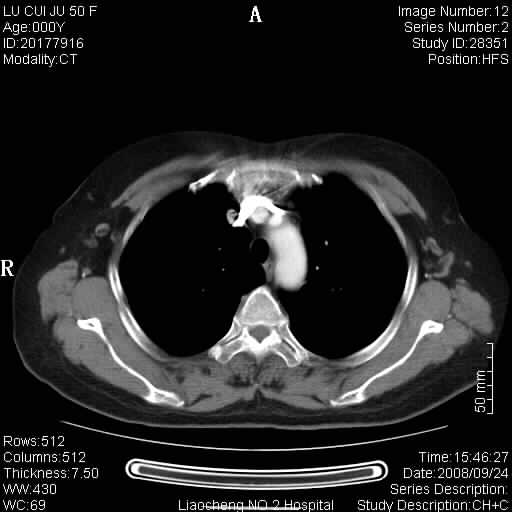

标题: CT15870:F50Y,纵膈占位,是不是胸腺瘤,请各位高手讨论。

临床表现为重症肌无力;ct增强扫描可见前纵膈胸腺部位弥漫性簇状软组织节结灶,不知道是不是胸腺瘤,请各位高手讨论。

考虑胸腺增生

胸腺外缘稍向外突,未见确切占位改变。结合临床考虑胸腺增生可能性大。

为未退化胸腺